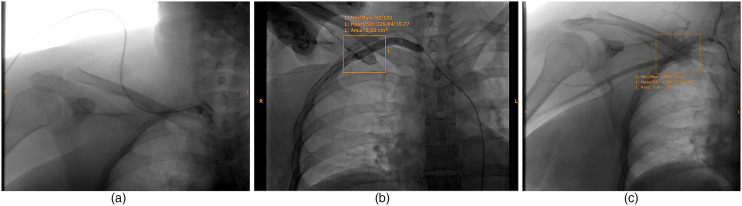

Accidental arterial puncture is a rare but significant complication associated with central venous catheterization. This report describes a case of inadvertent subclavian artery catheterization that was successfully managed with the ExoSeal vascular closure device. A female patient in her early 30s was hospitalized for severe acute pancreatitis that necessitated cannulation of the right subclavian vein. Postprocedure, infusion difficulties suggested a need for arterial catheterization, which was confirmed by imaging. The intervention resulted in prompt hemostasis and prevented further vascular injury, resulting in complication-free recovery. This case highlights the importance of rapid identification and treatment of arterial injury during central venous catheterization, and also demonstrates the effectiveness of ExoSeal in the management of vascular complications, especially in high-risk conditions.